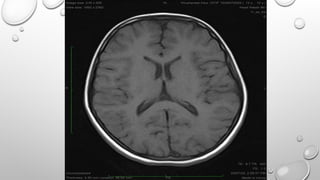

• THESE SEQUENCES ARE USED FOR 2D AND VOLUME ACQUISTIONS TO OBTAIN T1 WEIGHTED

BREATH HOLD IMAGES AS TR IS SHORT. THESE ALSO DEMONSTRATE GOOD T1 ANATOMY AND

PATHOLOGY AFTER GADOLINIUM CONTRAST.

SIEMENS SEQUENCES

FLASH MODIFICATION MEDIC

MP RAGE

IN PHASE OUT OF PHASE IMAGING